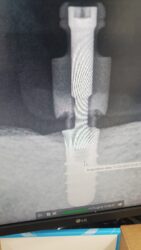

I have a patient with a fractured Straumann tissue-level implant at site #31. The coronal portion of the implant has fractured off circumferentially, leaving only the bone-level portion intact. This implant previously supported a gold crown on a one-piece abutment. Additionally, the tissue-level implant at site #30 has a worn… Read more

let me also clarify the PA. that is a Closed tray impression coping screwed on to the fractured implant.